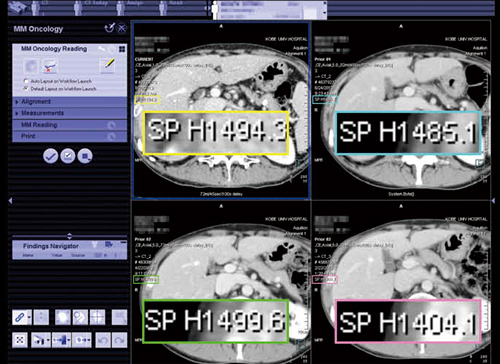

●MM Oncology

MM Oncologyでは,PET・SPECTなどの機能画像や,CT・MRIなどの解剖学的画像に対して,閲覧,操作,三次元処理,比較が行える。これまで,視覚的に比較し評価されてきた形態的・機能的な変化を,半自動的に解析,評価し,結果をレポートとして文書化することも可能だ。特に,強力な位置合わせ機能と,多様な測定ツールを備えていることが特長である。

1)強力な位置合わせ機能

syngo.viaの位置合わせ機能では,同じ患者の検査日の異なる複数のシリーズを読み込むと,何も操作することなく各画像のスライス位置が同期された状態で表示される(図3)。各画像のスライス位置の数値はバラバラであり,位置ではなく,形状からスライスを一致させていることがわかる。

図3 MM Oncology

位置合わせ機能で異なるシリーズを同期させて表示